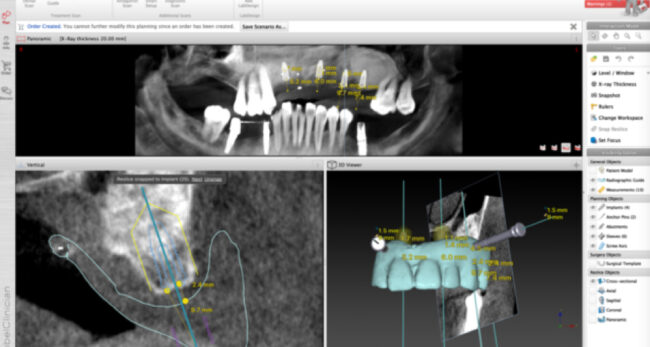

インプラント治療症例

治療開始時:下のインプラントの被せ物を作り直したいという主訴で来院されました。